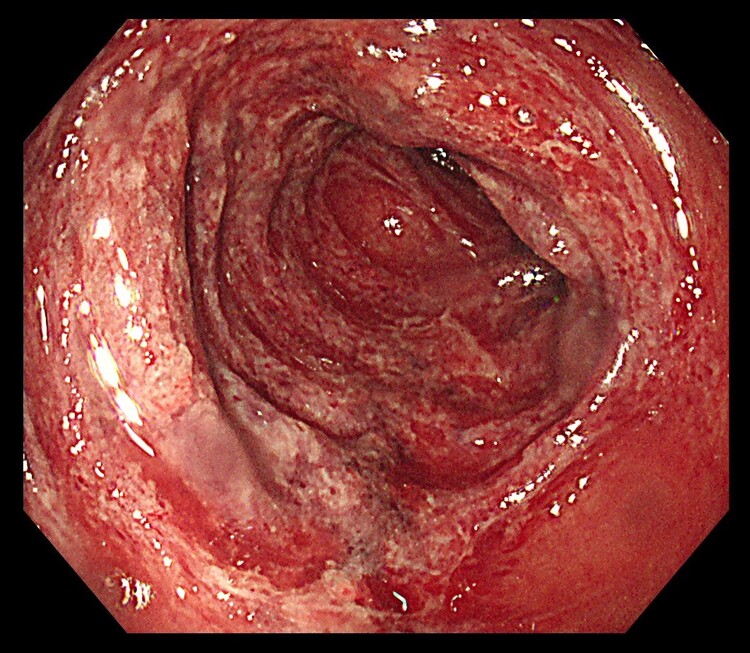

大腸がん

大腸がんは悪性疾患で、進行すると命に関わる病気です。

初期の大腸がんは、症状は特に出ませんが、進行すると、

- 血便や下血

- 下痢と便秘の繰り返し

- 細い便

- 腹痛

- お腹の張り

- 体重減少

などの症状が現れます。

特に肛門近くのがんでは、痔と見分けがつきにくい赤い血が出ることもあります。

また、痔と大腸がんが同時に存在している場合もあり要注意です。

大腸がんは大腸内視鏡検査で早期発見することができます。

「赤い血だから痔からの出血だろう」と自己判断して放置せずに、出血がある場合は必ず医療機関を受診してください。